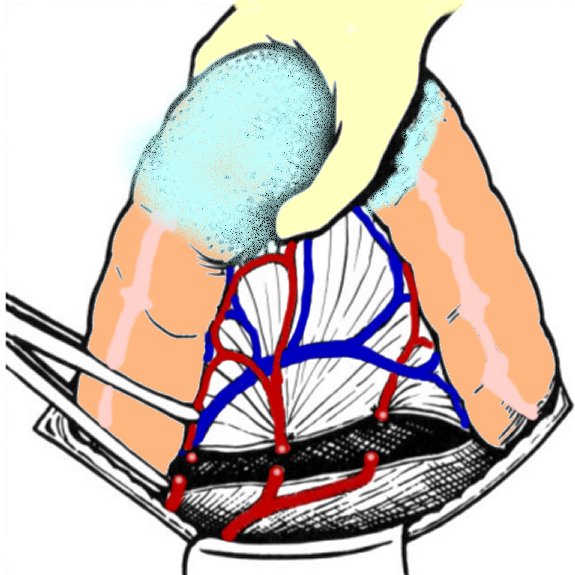

COLECTOMIA SEGMENTARA SIGMOIDIANA - CHIRURGIE

COLECTOMIA SEGMENTARA SIGMOIDIANA - CHIRURGIE I. DEFINITIE Este interventia, prin care se extirpa cea mai mare parte a ansei sigmoidiene mobile si se reface continuitatea digestiva prin anastomoza colo-rectala. II. ISTORIC Citeste tot ... 3131 cuvinte